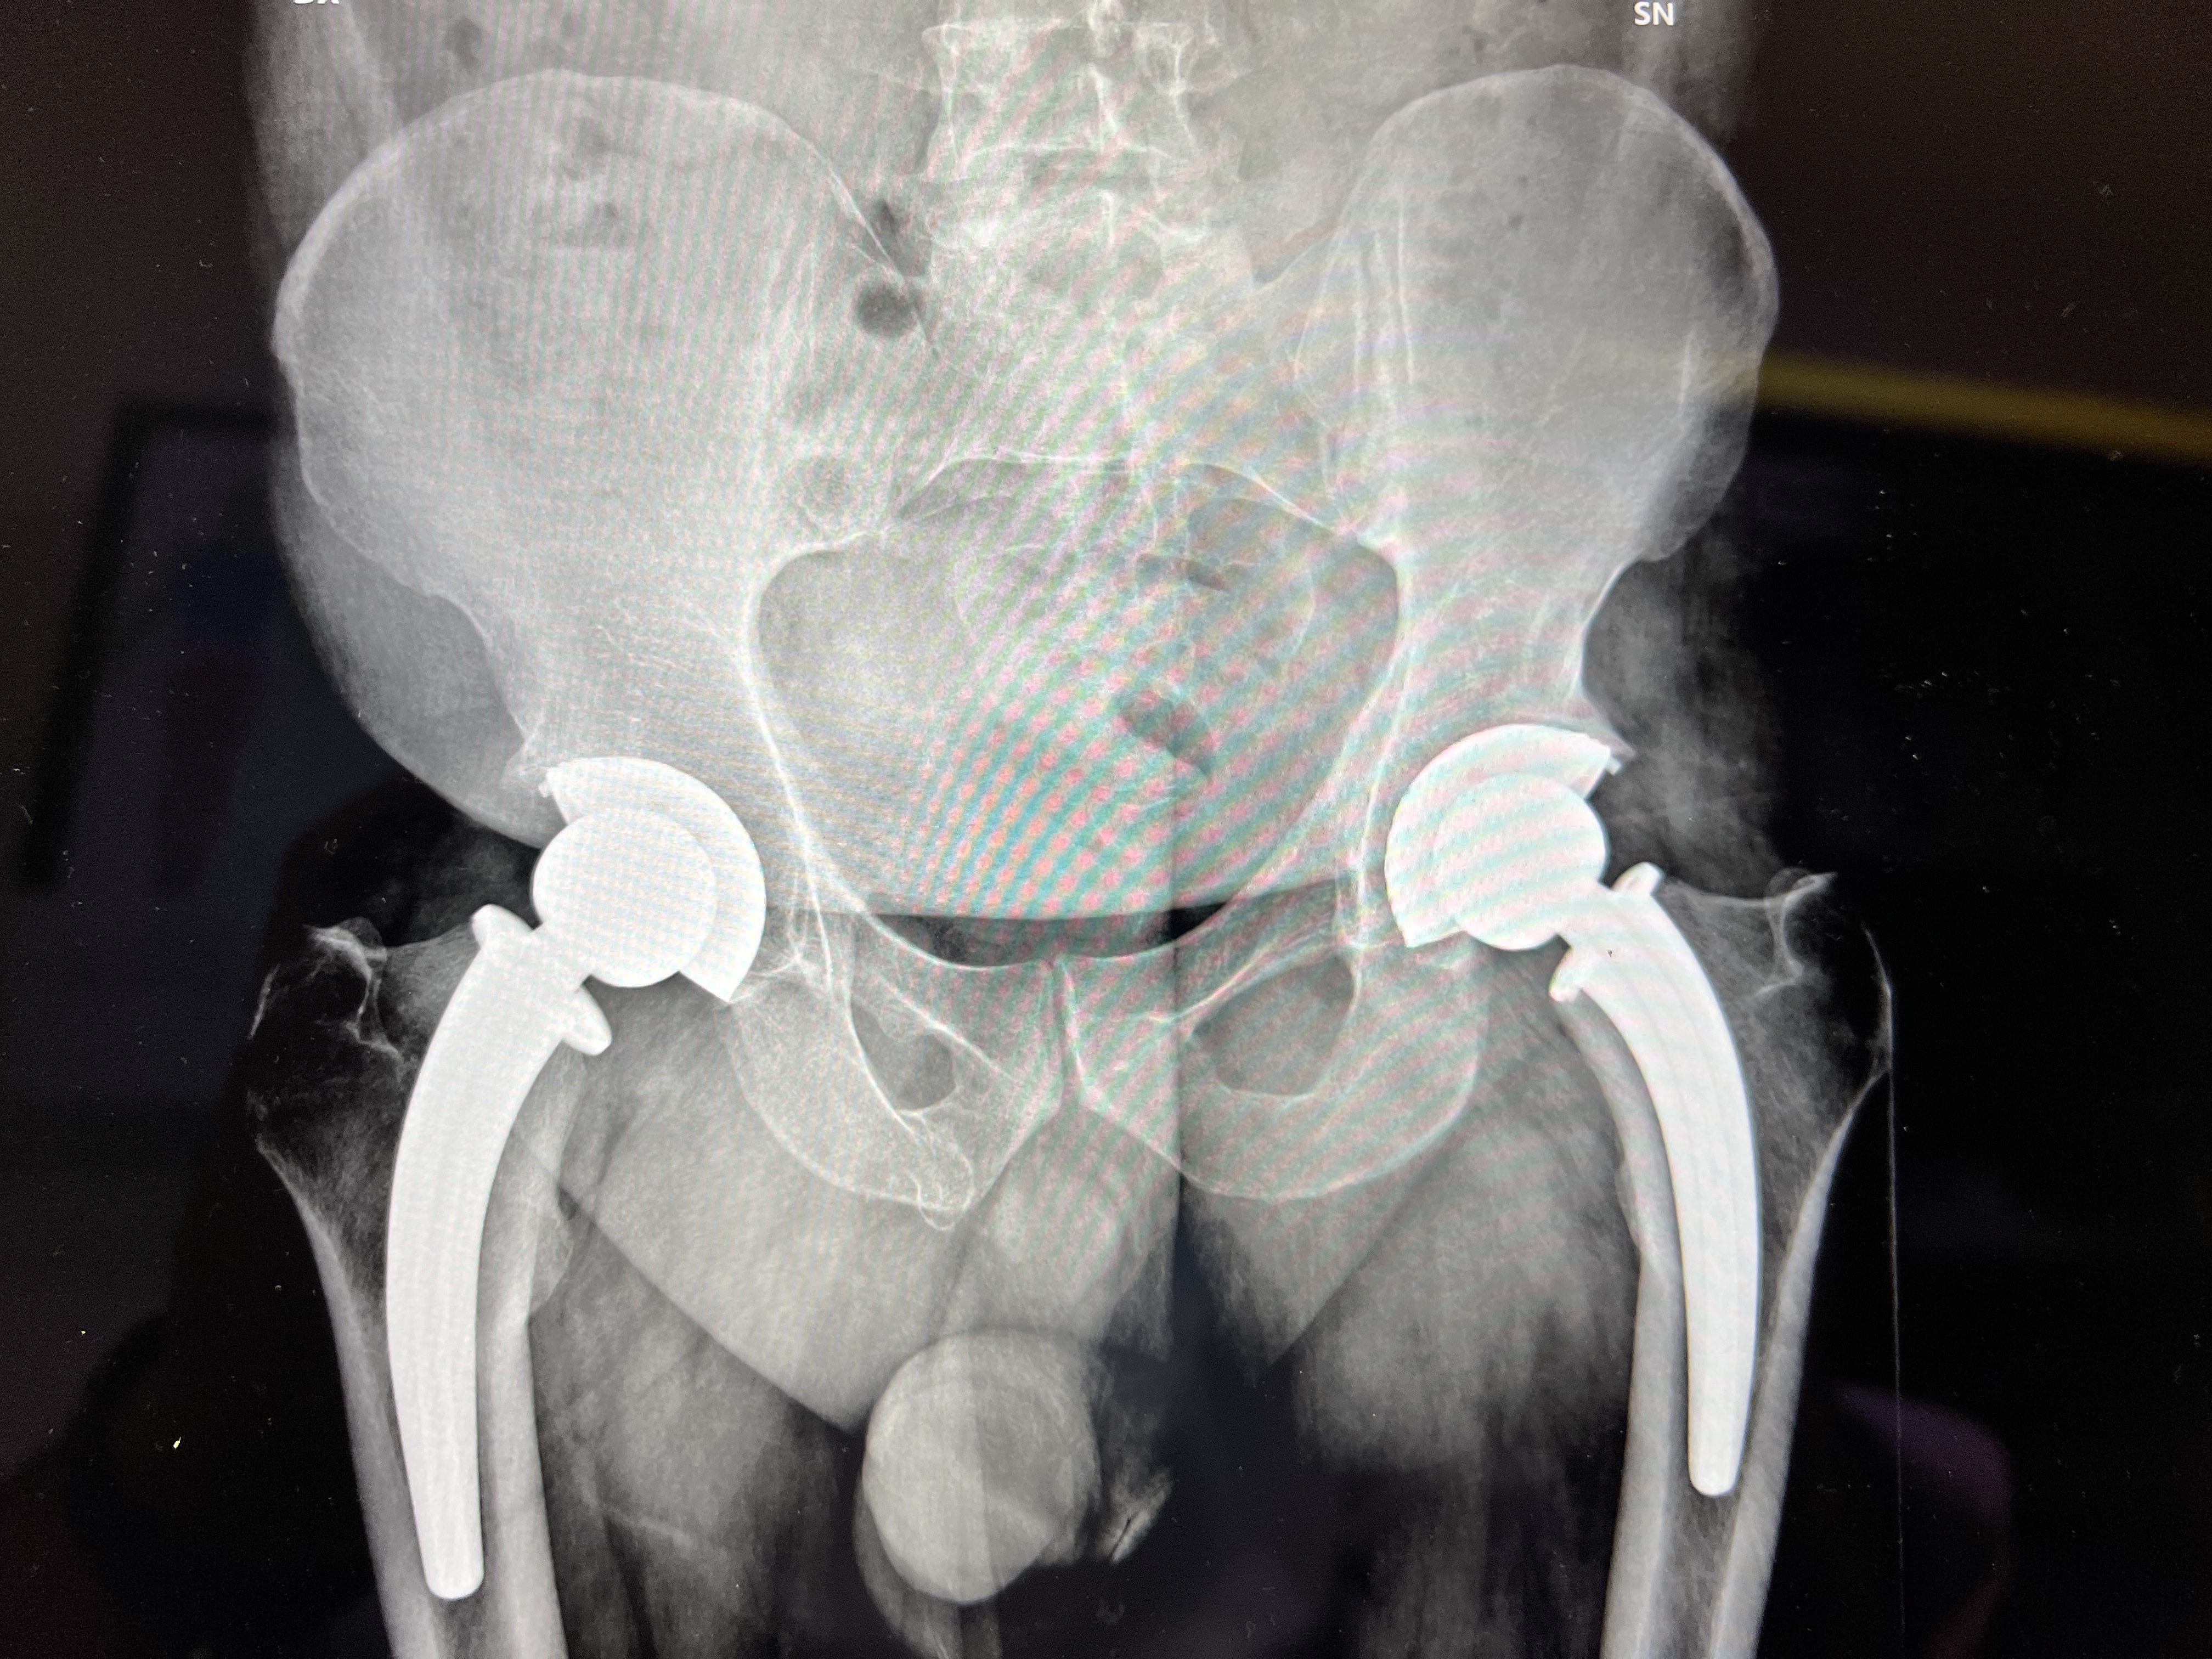

Protesi Totali d'Anca bilaterali – proiezione AP.